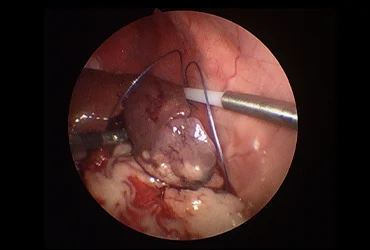

(진단/협진 사례: 간염 환자의 복강경 생검, 간종양 환자의 경우 외과 협진을 통한 복강경 종양 제거 계획 수립)

치료 과정에서 외과와의 긴밀한 협력을 통해 담낭 절제, 종양 제거, 장관 이물 제거 등 필요한 수술적 처치를 원활하게 연계하며,

중증 환자의 경우 응급중환자의학과와의 협진을 통해 집중적인 관리를 제공합니다.